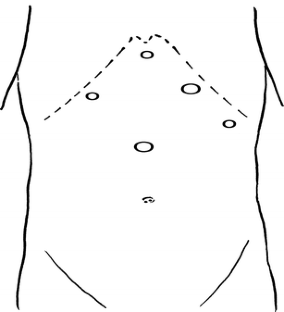

Fig. 1